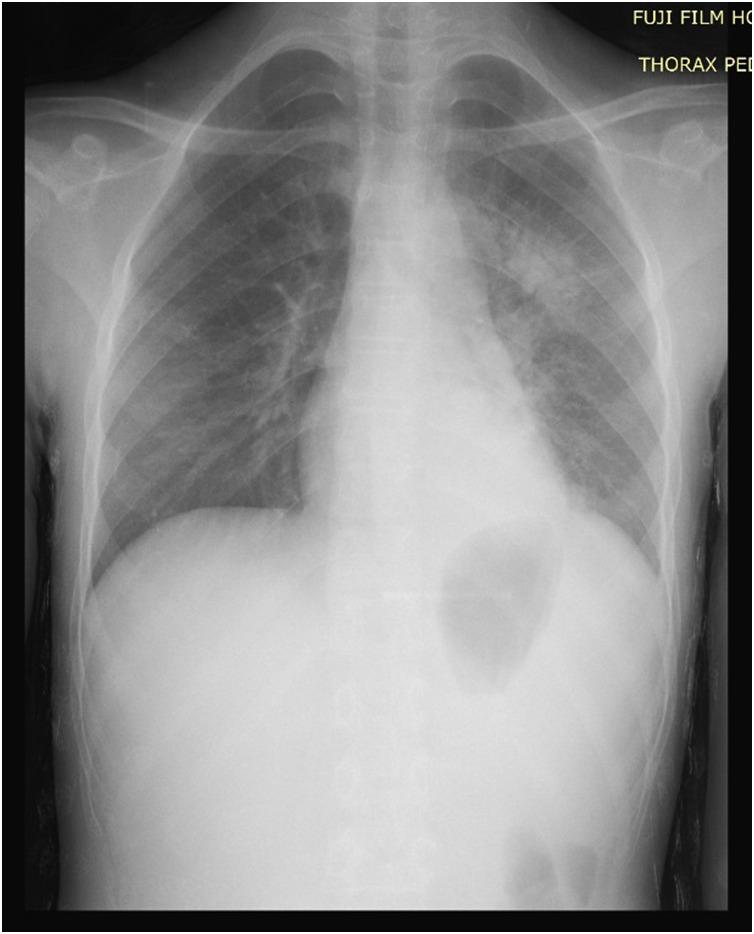

Rib osteomyelitis is a rare disease, occurring in ~1% or less of all cases of haematogenous osteomyelitis. During the last century, 58 cases of rib osteomyelitis were reported in the literature, of which, multiple ribs were involved in only five patients. Because of its rarity and non-specific clinical signs, diagnostic of rib osteomyelitis may be delayed. We report a case of multifocal rib osteomyelitis revealed by a dorsal mass in a healthy 13-year-old female child.

肋骨骨髓炎是一种罕见疾病,在所有血源性骨髓炎病例中发生率约为1%或更低。在上个世纪,文献报道了58例肋骨骨髓炎病例,其中仅有5例累及多根肋骨。由于其罕见性及非特异性临床症状,肋骨骨髓炎的诊断可能会延迟。我们报告一例13岁健康女童因背部肿块而被发现的多灶性肋骨骨髓炎病例。